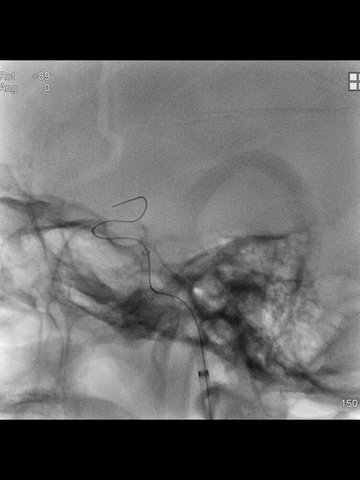

鉴于术前CT提示血栓范围长和负荷大,故于微导管送入一长取栓支架(4*40mm),争取一次取栓成功;支架释放后造影见:闭塞段少许前向血流,证实取栓支架已覆盖长段血栓,支架远端超出血栓远端一段较长距离。

透视下,利用支架锚定作用,将中间管头端推至ICA末端;而后中间管接50ml注射器(血管钳辅助下,保持负压状态),回撤取栓支架同时前送中间管,直至其头端达M1远端。

撤出取栓支架后,负压状态下缓慢回撤中间管,直至海绵窦段时才见回血通畅;此时见支架取栓和导管抽吸取出大量红色血栓。